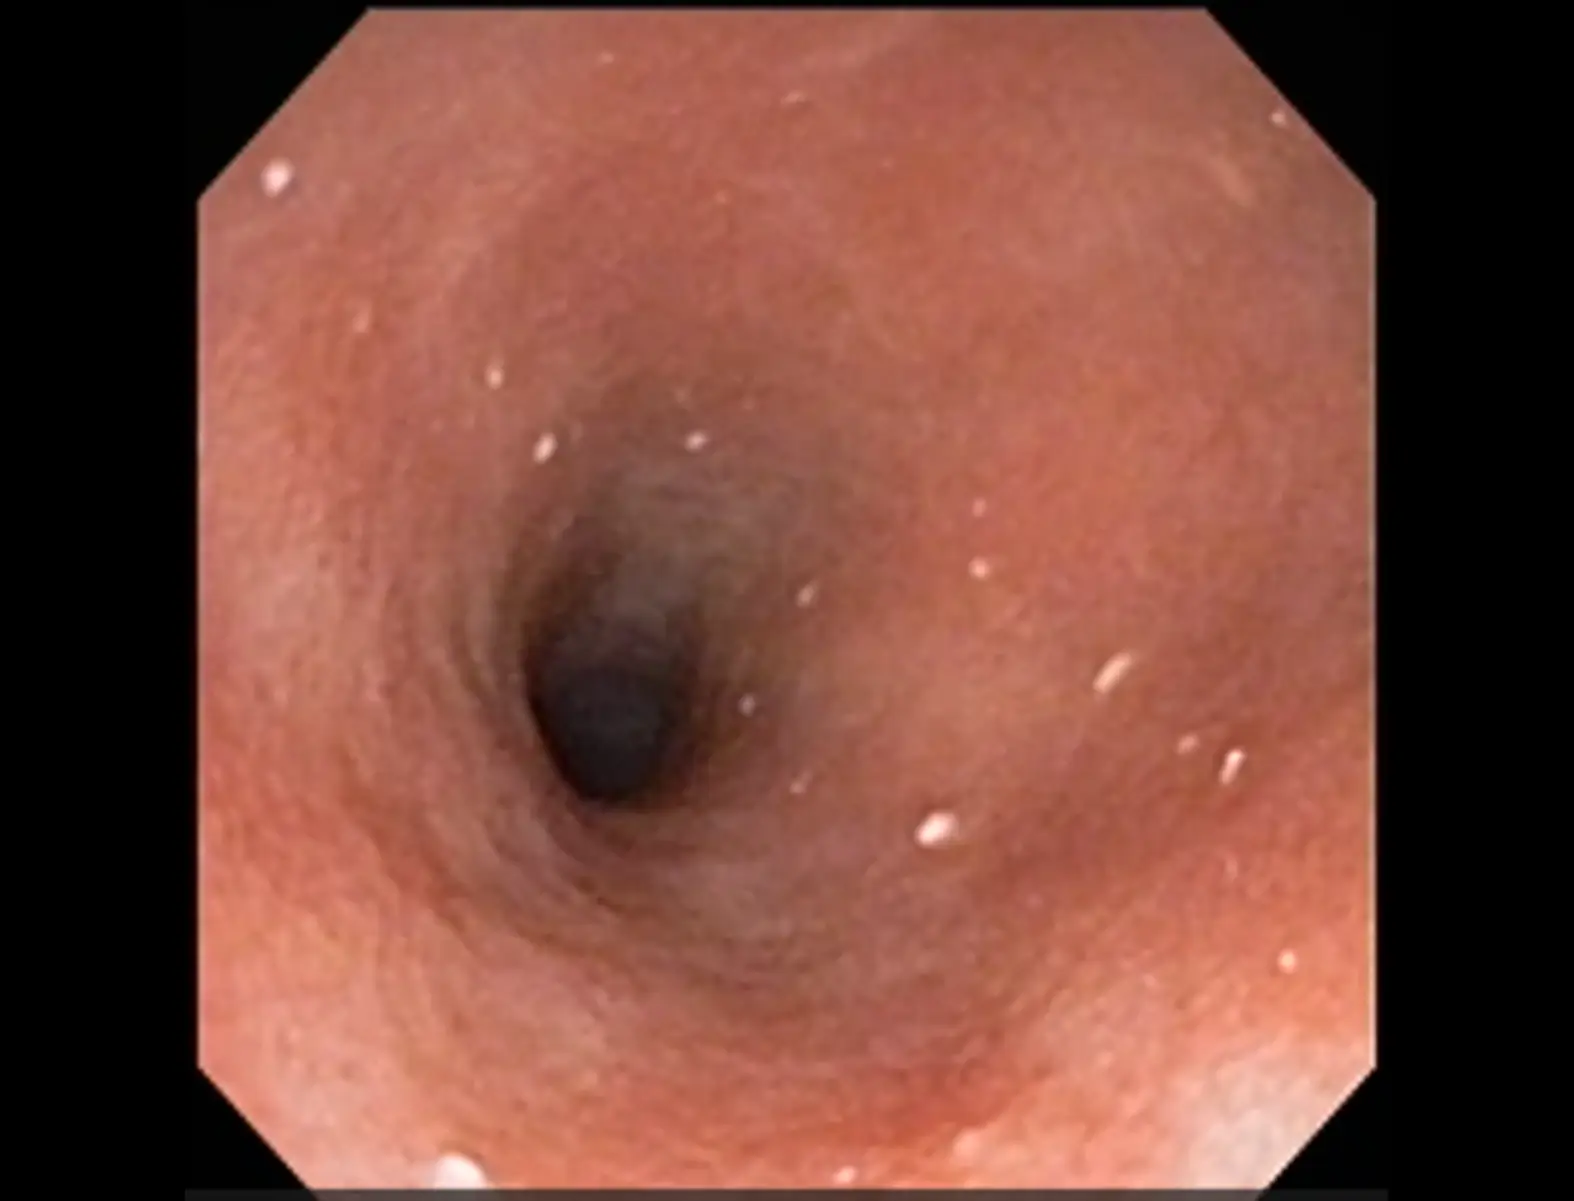

内視鏡検査

食道・胃腸内部を詳細に評価します。また異物摘出やポリープ切除などは同時に治療を実施することができます。

内視鏡手術

慢性腸症の場合には治療が長期に渡ることがあります。長期の治療には正確な診断を行って納得感のある治療選択が重要です。正確な診断のためには病理検査が必要ですが、開腹手術より低侵襲な内視鏡検査や手術を希望されるご家族さまが増えています。